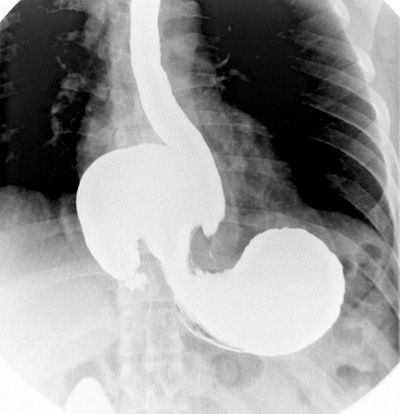

Рентген с контрастом

Не всегда эндоскопические исследования возможны, поэтому иногда применяют рентгенографический метод. Чтобы лучше просматривалась поверхность желудка, пациент перед началом выпивает специальный контраст. Рентген позволяет увидеть полипы, оценить их размер и количество, но такой наглядности, как эндоскопия, он не дает. Подобный способ диагностики запрещен тяжелобольным, беременным и пациентам с внутренним кровотечением.